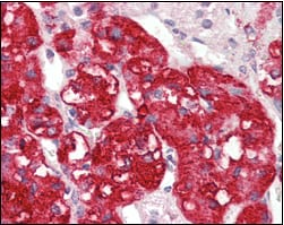

IHC    1/200 - 1/1000